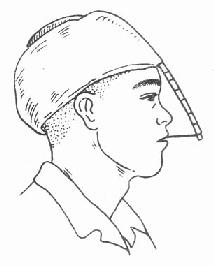

2.牵引复位:颌骨骨折后,经过较长时间(上颌骨三周以上,下颌骨四周以上),骨折处已有部分纤维组织愈合,手法复位不成功,可采用牵引复位法。下颌骨骨折多用颌间牵引,就是在下颌骨有移位的骨折段上安置分段牙弓夹板(图4-16),然后在与上颌的牙弓夹板之间,用小橡皮圈作弹性牵引,使之逐渐恢复正常的咬合关系。上颌骨骨折后,如骨折段向后移位,可在上颌牙列上安置牙弓夹板,在头部制作带有金属支架的石膏帽,在牙弓夹板与金属支架之间作弹性牵引,使上颌骨骨折段向前复位(图 4-17)。需要较大牵引力时,也可作卧式重力性牵引。

| 图4-16 分段式牙弓夹板 | 图4-17 金属支架石膏帽,将上颌骨骨折段向前牵引复 |